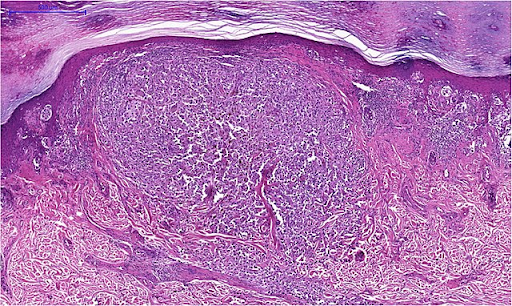

La diagnosi certa di melanoma si ottiene invece solo dopo una biopsia, ossia il prelievo e analisi microscopica di un campione di tessuto.